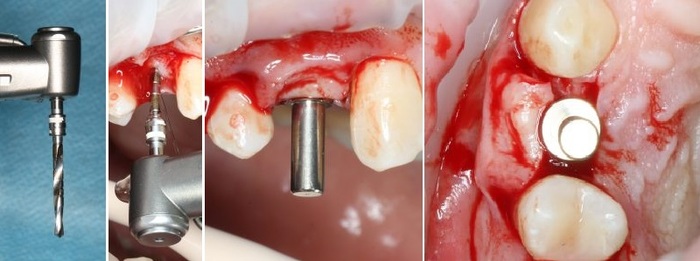

Далее проводится подготовка лунки под имплантат (препарирование)

Имплантация начинается с разметки. Проводится это при помощи шаровидного бора

Далее, с помощью пилотной фрезы диаметром 2 мм задаётся ось лунки будущего имплантата, которую контролируем при помощи пинов*

*Штуковина для контроля положения имплантата

Далее, коль ось лунки задана правильно, нам остаётся лишь довести лунку до нужного диаметра. Для этого используются основные рабочие фрезы. Первая из них — диаметром 3.0 мм:

После чего — контроль положения с помощью входящих в набор аналогов имплантатов

На очереди следующая фреза, диаметром 3.4 мм:

И теперь на очереди самый ответственный этап — финишная фреза для нашего имплантата диаметром 3.8 мм. Теперь мы понижаем обороты на физиодиспенсере до минимума, чтобы избежать перегрева и травмы костной ткани, после чего очень-очень аккуратно проходим лунку:

Еще раз проверяем все с помощью аналогов имплантата. Как говорится, семь раз отмерь, один воткни:

Мы довели лунку до глубины 11 мм и диаметра в 3.8 мм. Но на этом подготовка лунки не заканчивается.

А всё потому, что костная ткань — упругая среда, и чтобы снять напряжение с кортикальной пластинки (и предотвратить периимплантит) мы используем специальную кортикальную фрезу:

При работе с очень плотной костной тканью мы дополнительно используем специальный метчик: